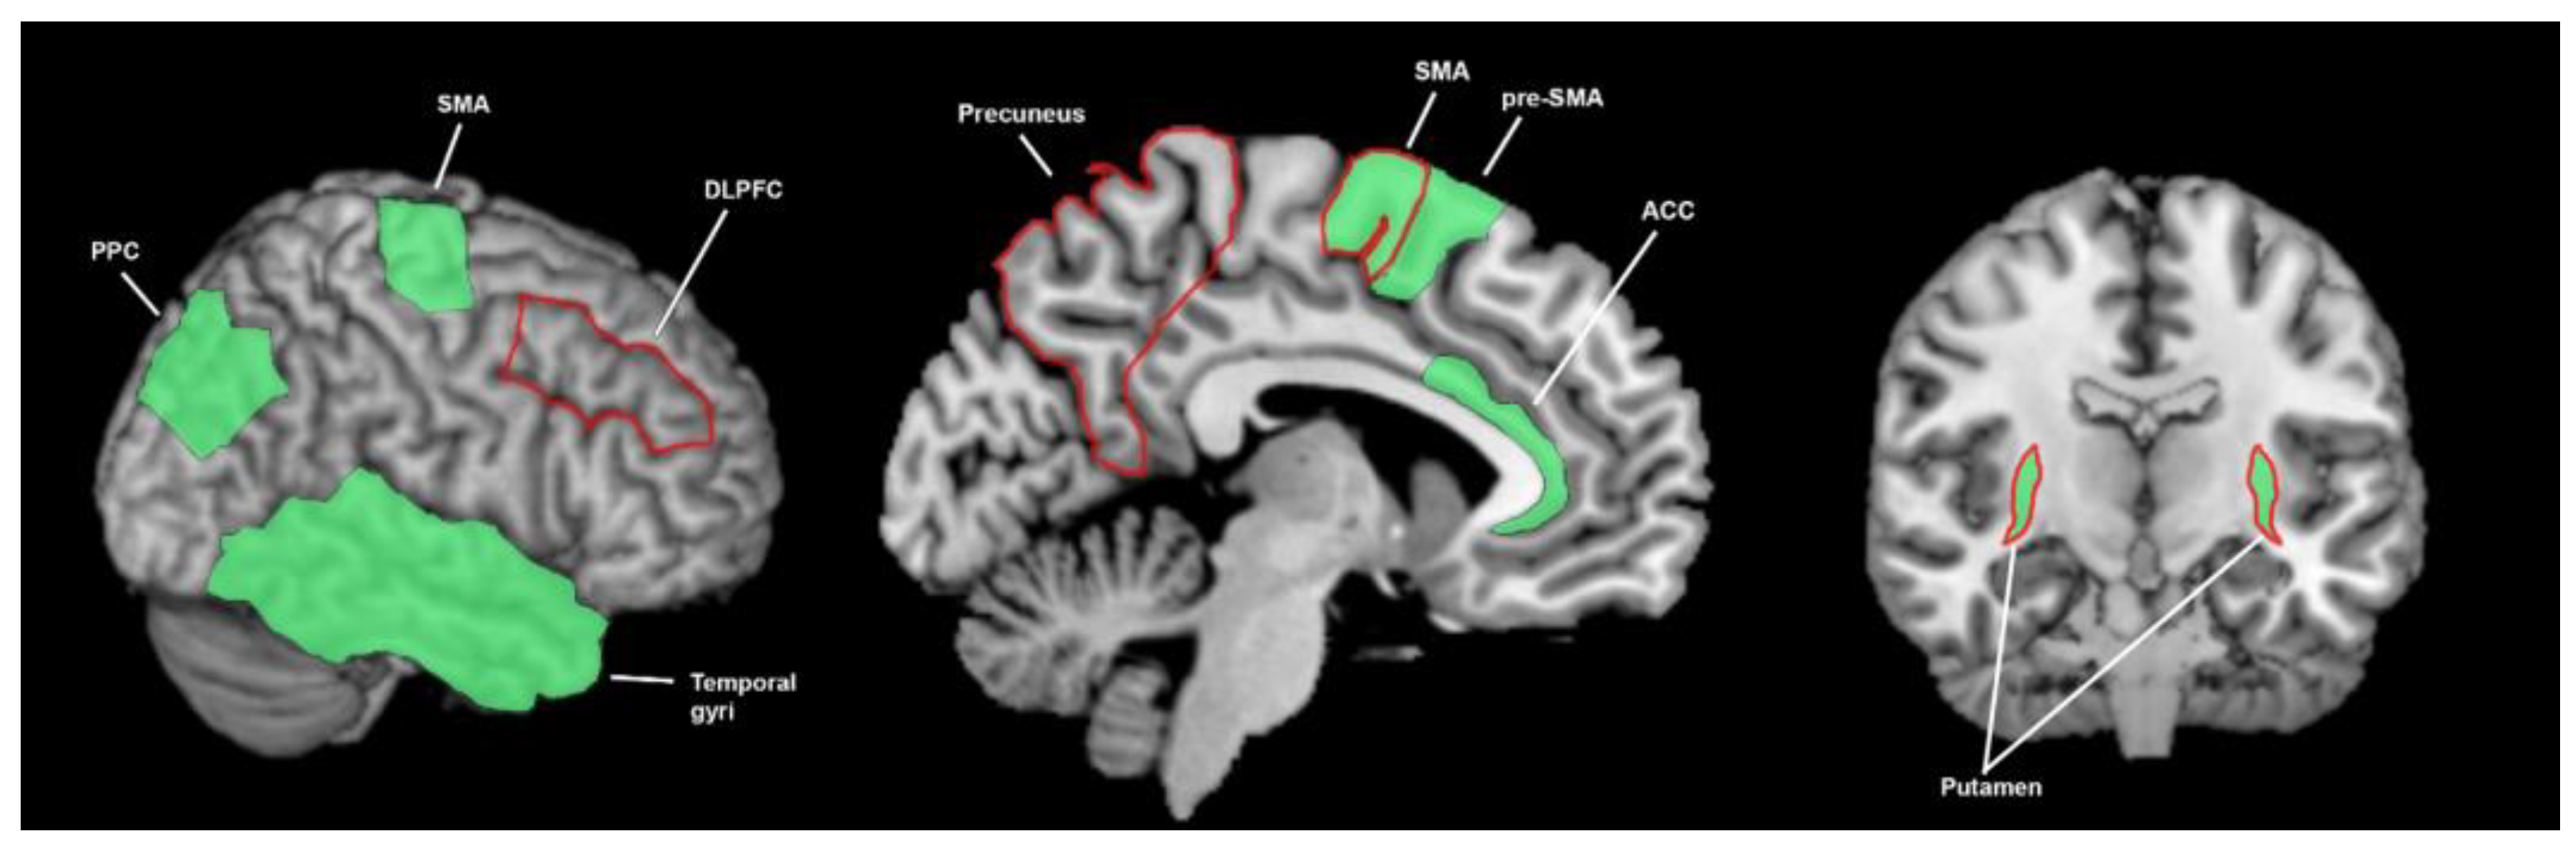

3.3. What Brain Areas Are Involved in Sensory Processing?

3.3.1. What Brain Areas Are Involved in Temporal Processing in Healthy Cohorts?

3.3.2. What Brain Areas Are Found to Function Abnormally in Temporal Processing in People with Parkinson’s Disease?

3.4. The Breadth of Sensory Response and Multisensory Response of the Basal Ganglia

4.1. What Brain Areas Are Involved in Sensory Processing, What Are the Abnormalities in Parkinson’s Disease, and What Is the Importance of the Basal Ganglia?